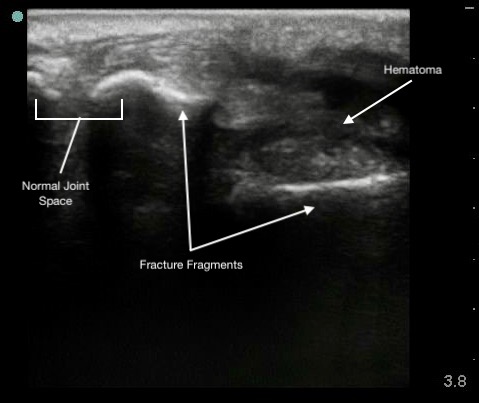

Figure 6.

Colles (distal radius) fracture.

Hypoechoic hematoma or effusion may be visible in the surrounding soft tissue.

Ultrasound allows immediate assessment of the presence and extent of a fracture at the area of tenderness.

Capable of detecting displacement as small as 1 mm.

Ultrasound guidance can enhance the effectiveness of hematoma blocks by ensuring accurate anesthetic delivery.